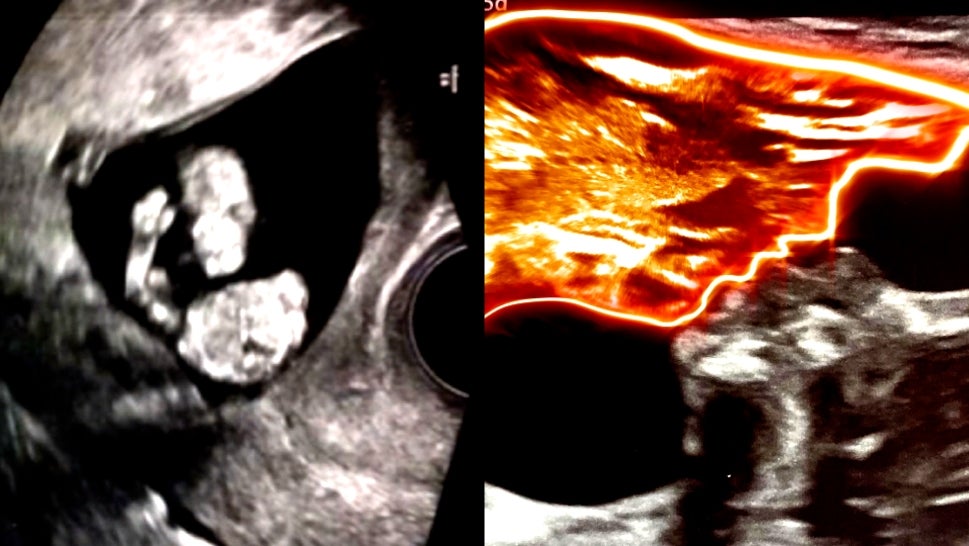

These Are the Strangest Things Seen in Sonograms